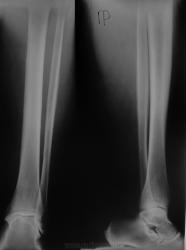

Вот для сравнения контрлатеральная

Для исключения костной патологии-выполнить Р-граммы котей здоровой голени.